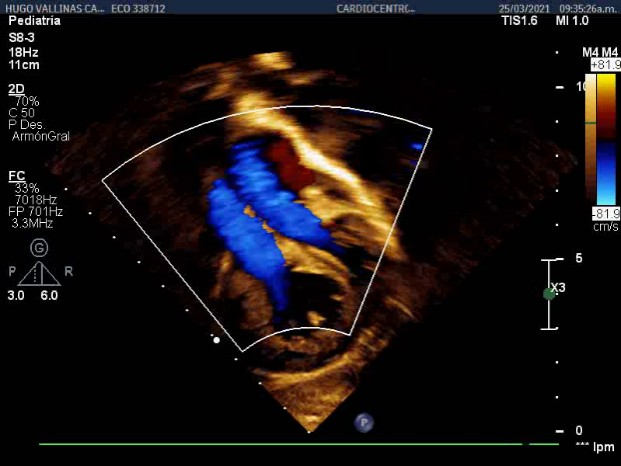

Hemoglobin: 17g / dl Hematocrit: 0.54 Leukocytes: 15x109 / l Segmented: 14% Lymphocytes: 84% Platelet count: 302 x10 9 / l Creatinine: 67 mmol / l Glycemia: 7.3mmol / l, D-dimer positive, with slight metabolic and lactic acidosis 5.1mmol / l.Chest radiograph with evidence of bilateral inflammatory-looking lesions (Figure 1).

Figure 1 AP chest X-ray. Bilateral inflammatory lesions are seen.

Positive covid

During admission, invasive mechanical ventilation was not necessary, he underwent symptomatic treatment15 for fever with dipyrone, administration of fraxiheparin (0.3 vial/12h) for 5 days and required antibiotic therapy with Ceftriazone for a period of 10 days at doses of 150mg / kg / day, as well as dexamethazone.Under the criteria of clinical and radiological improvement, as well as the Covid-19 infection ruled out through a virological study, the patient was discharged after 20 days, with subsequent follow-up.He was evaluated during three months after discharge by Cardiology at the William Soler Cardiocenter, serial evaluation of EKG and chest X-ray.

The chest X-ray showed microatelectasis lesions and slight pulmonary edema.